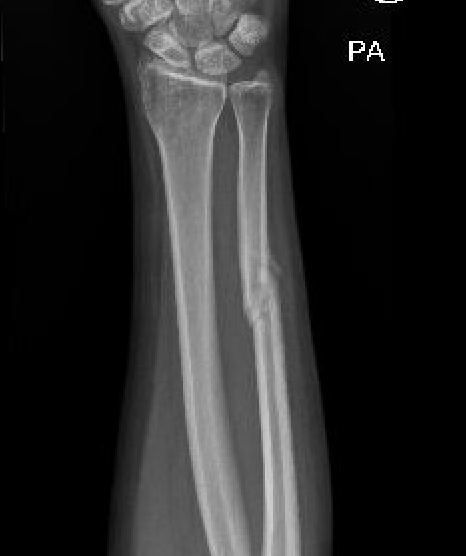

Minimally displaced fractures

- < 50% displaced

- < 10 degrees angulation

Results

Long arm cast not necessary

Increased nonunion rates with midshaft versus distal fractures

- increased nonunion with midshaft (30%) versus distal 1/3 fractures (2%)